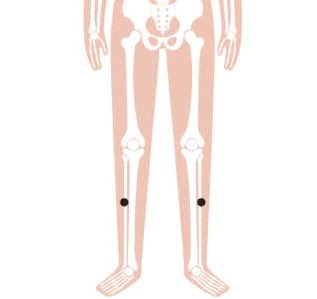

4. Fenglong

Fenglong, ofwel Maag 40 (ST40), wiens Chinese naam zich vertaalt naar ‘overvloedige overvloed’, is een punt dat zeer geschikt is om damp af te voeren. In TCM is overmatige gewichtstoename meestal te wijten aan de ophoping van damp. Dit acupunctuurpunt reguleert voornamelijk het maagdarmkanaal, verwijdert lichaamsvloeistoffen, voedt de milt en de nieren, brengt Qi (energie) en bloed in evenwicht. Dit zorgt er dan vervolgens voor dat zwaarlijvige mensen gewicht kunnen verliezen.